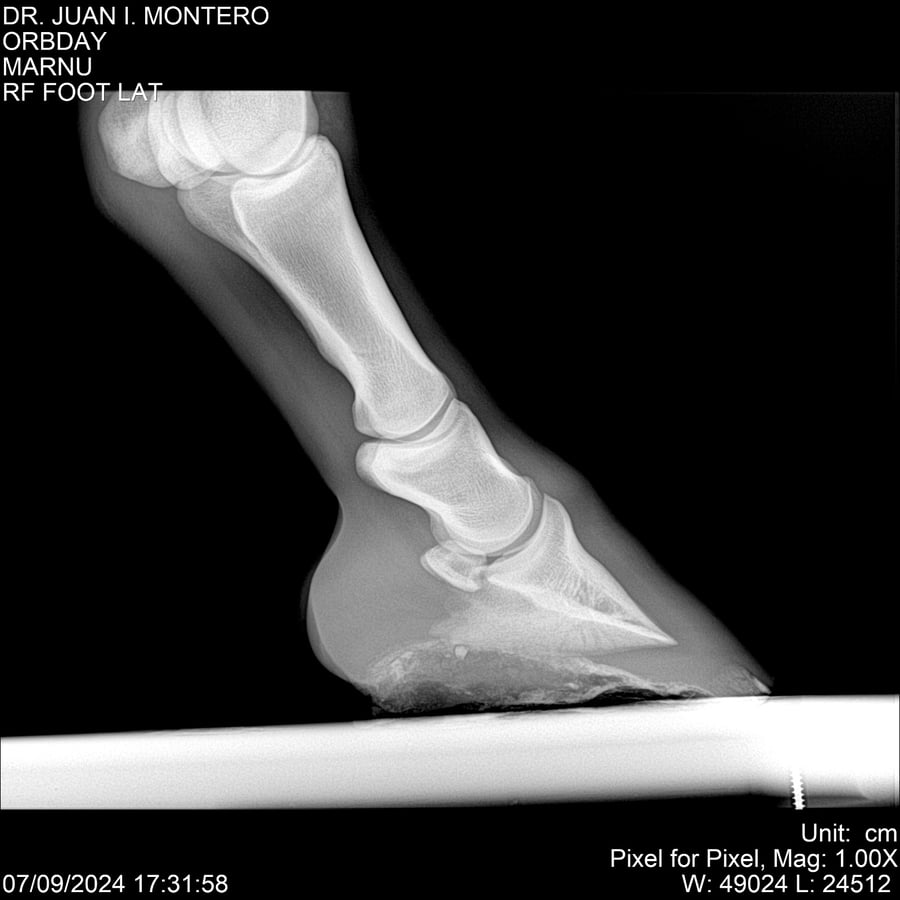

• Empresa: Abelenda N. R., Walter Hugo